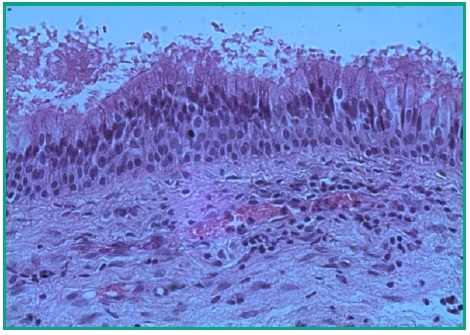

Examen Microscópico: Cavidad quística revestida por membrana fina constituída por epitelio seudoestratificado cilíndrico ciliado (mucosa sinusal), que alterna con zonas de hiperplasia, respaldada por un tejido conectivo fibroso, con zonas edematosas, con abundantes capilares algunos de ellos congestivos y exudados inflamatorios mixtos. El contenido es eosinófilo amorfo con células inflamatorias (linfocitos y plasmocitos) dispersas en un material mucoso (Figs. 13, 14).